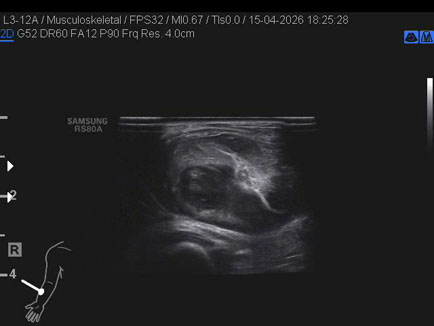

Data inserimento: 17/04/2026

Ecografia del: 15/04/2026

Strumento: Samsung

Sonda: Lineare

Commento all'esame: ematoma post trauma da sforzo del lungo supinatore dx in anziano sottoposto a terapia con i NAO.

Conclusioni: ematoma del muscolo lungo supinatore destro (hematoma of the right supinator longus muscle).